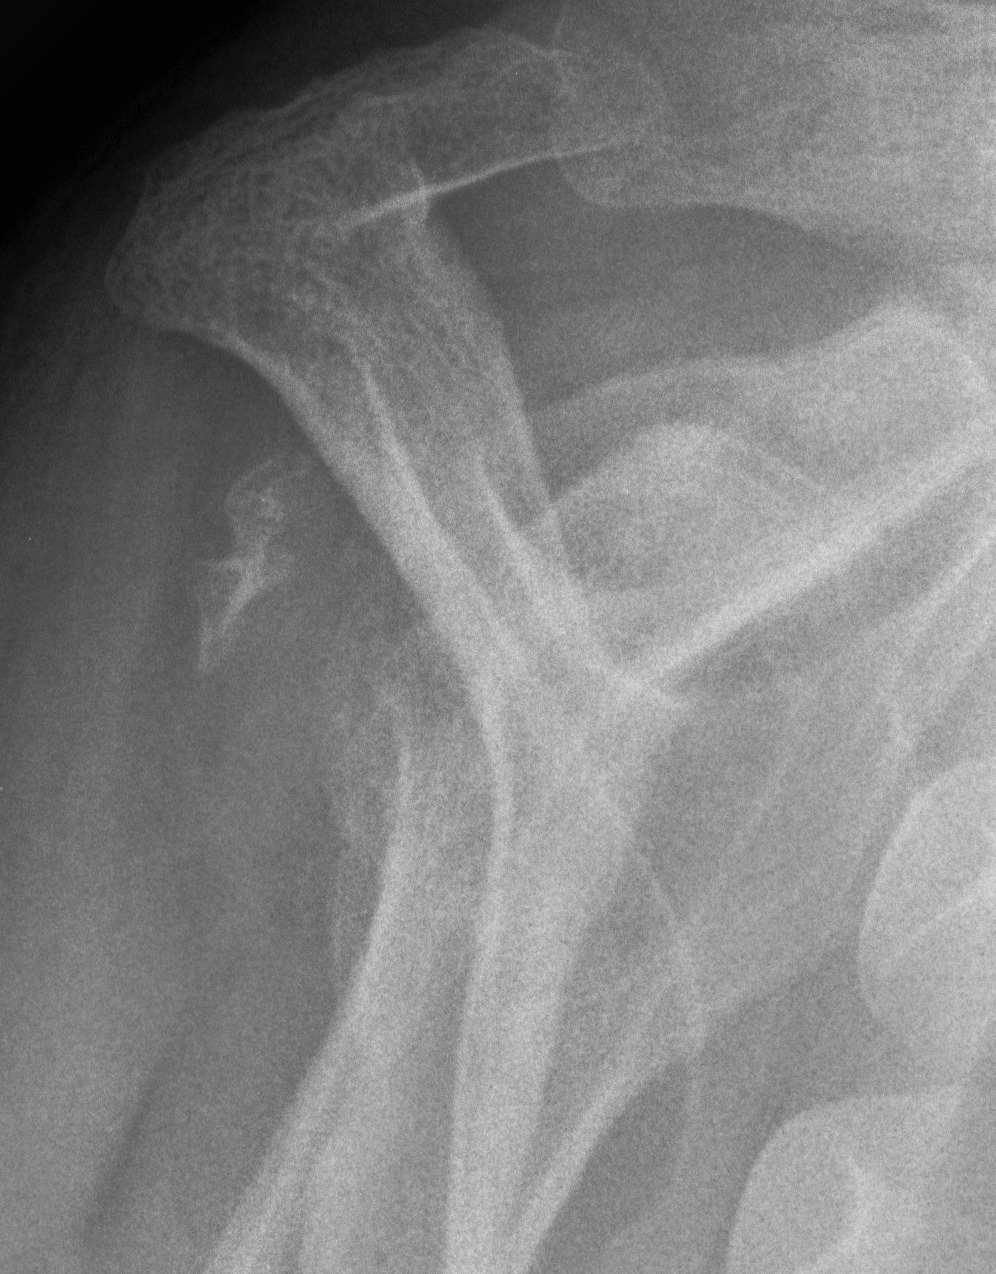

Xray

Signs of chronic shoulder dislocation